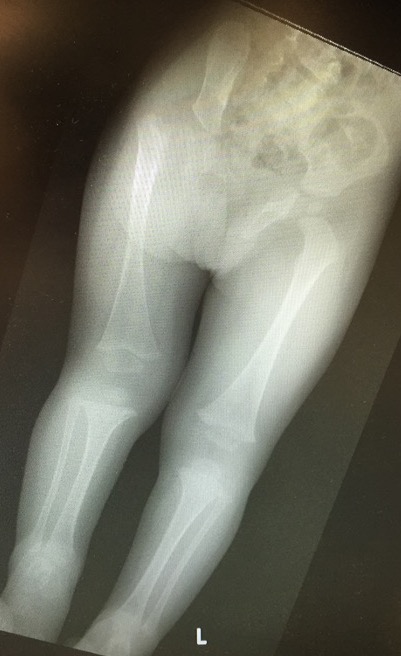

Child with very short leg

- large shoe raise

- LLD above GT

- short involved thigh segment

- characteristic posture (Flex / Abducted / ER hip)

4. LLD

5. Inadequate lateral femoral condyle